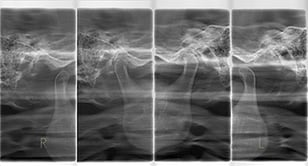

ひずみの少ない像で顎全体が写るパノラマレントゲンのみならず、顎関節撮影、矯正治療で必要なセファロレントゲンも撮影できます。